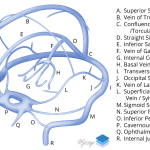

- Hyperattenuating appearance of the superior sagittal sinus, straight sinus, bilateral tentorial and cortical veins, both transverse sinuses, and the confluence of sinuses

Findings concerning for thrombosis of the superior sagittal sinus, straight sinus, bilateral tentorial and cortical veins, both transverse sinuses, and the confluence of sinuses. Recommend brain MRI with and without contrast for further evaluation.